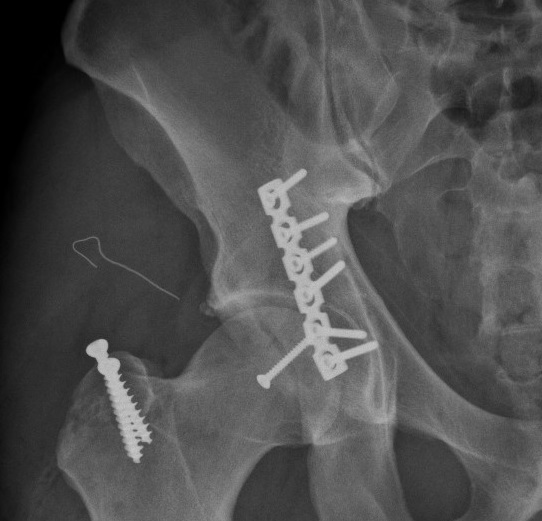

Các bác sĩ Vinmec đã mổ nắn trật khớp, đồng thời kết xương bằng nẹp vít ổ cối để xử trí tai nạn trật khớp háng cho anh Dustin.

Chấn thương của anh Dustin khá hiếm gặp, vùng tổn thương ở sâu, vi trường phẫu thuật hạn chế, xung quanh các mảnh vỡ là dây thần kinh và mạch máu quan trọng. Với ca chấn thương này, TS Nghĩa và các bác sĩ Vinmec đã tiến hành nắn trật khớp trở lại, đồng thời kết xương bằng nẹp vít ổ cối thành công cho người bệnh trong ca mổ kéo dài hơn 4h. Ba ngày sau mổ, Dustin đã bắt đầu tập đi. Và 6 ngày sau, anh đã được ra viện, đồng thời định kỳ đến tập phục hồi chức năng theo các bài tập chuyên sâu tại bệnh viện.